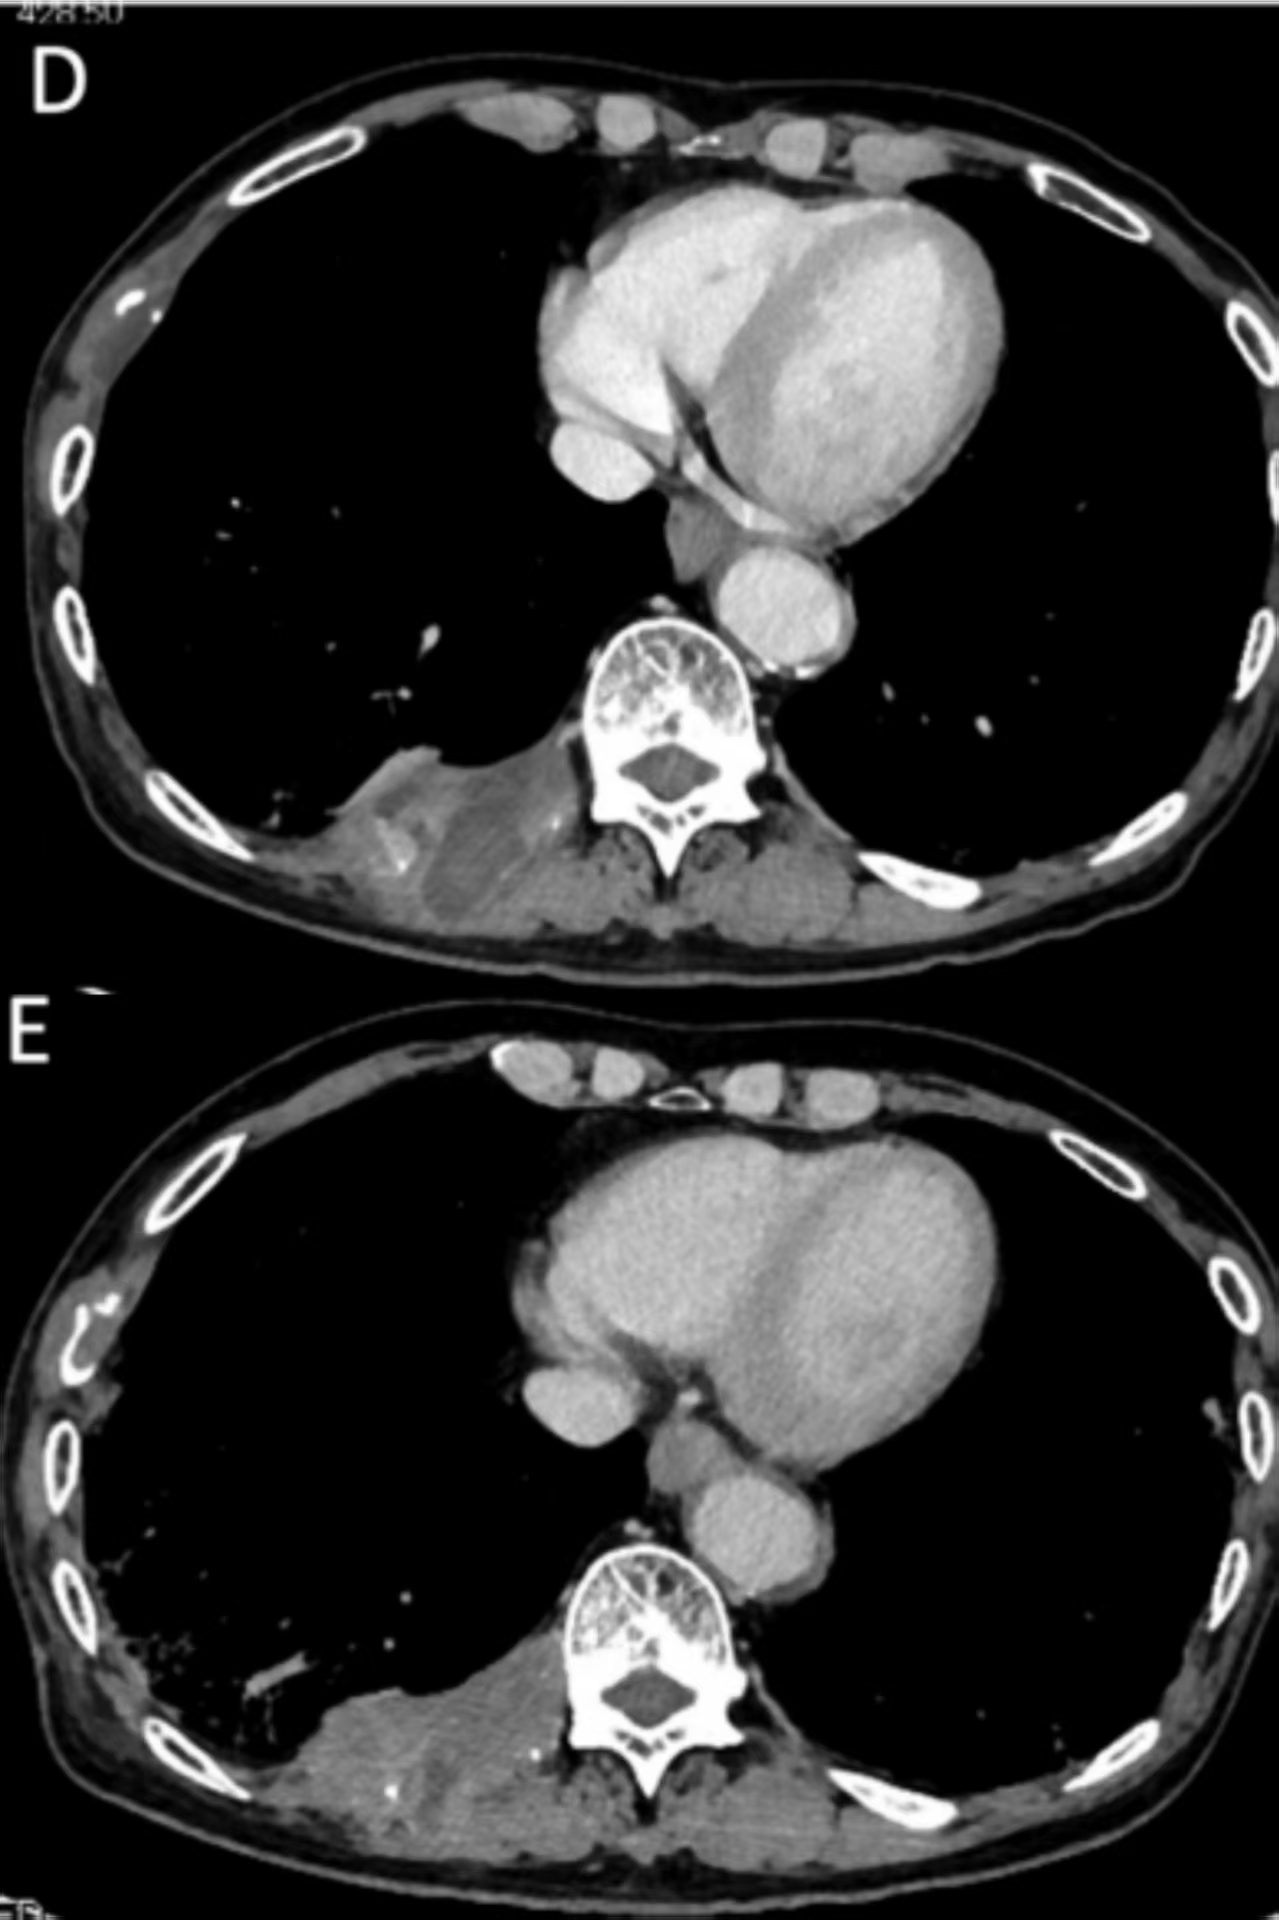

2018年,美国人克里斯·怀特(Chris White)被诊断出罕见的转移性黏膜黑色素瘤,癌细胞已扩散至肺、肝和淋巴结。在经历了手术、化疗、放疗乃至免疫检查点抑制剂治疗后,病情仍在无情进展。主治医生甚至开始与他讨论临终关怀的安排。然而,一次勇敢的尝试彻底改写了他的命运:他加入了一项肿瘤浸润淋巴细胞(TIL)疗法的临床试...